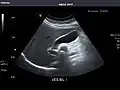

Abdominal Ultrasound (Full Exam)

STRUCTURED REPORT

(Technique: Transabdominal ultrasonography; Device: Toshiba Aplio XG)

Liver: Diffusely homogeneous and normal in echogenicity. No focal mass or contour nodularity. No intrahepatic biliary ductal dilatation.

Portal Vein: Patent main portal vein.

Gallbladder: No stones, wall thickening, or pericholecystic fluid.

Common Bile Duct: Nondilated measuring 1.3 mm at the level of the porta hepatis.

Pancreas: Visualized portions unremarkable.

Spleen: Normal in size.

Kidneys: Right and left kidneys measure 11.5 cm and 12 cm in length respectively. No hydronephrosis. Small left lower pole kidney cyst.

Ascites: None.

Aorta: Visualized portions normal in caliber, 16 x 15 mm.

IVC: Normal.

IMPRESSION:

Normal abdominal ultrasound.

Pancreas